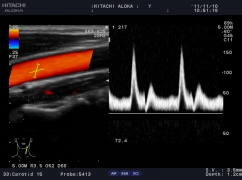

精確血流成像

智能識別血流運動和組織運動,使血流更充盈,組織邊界更清晰。

自動IMT測量

自動IMT檢測與手動測量相比提高了準確性,更方便,分辨率為0.01mm。系統(tǒng)可以自動描記并顯示結(jié)果和直方圖,直方圖可以更加直觀的觀察病變數(shù)據(jù),為動脈硬化的準確診斷提供了更為方便的工具。